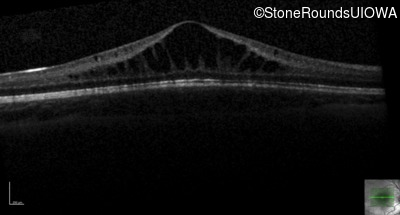

This 6 year old boy first experienced difficulty reading and seeing the blackboard at age 5.

| Age at visit: 6 years |

| Age at visit: 11 years |

| Age at visit: 14 years |

| Age at visit: 14 years (Visit 2) |